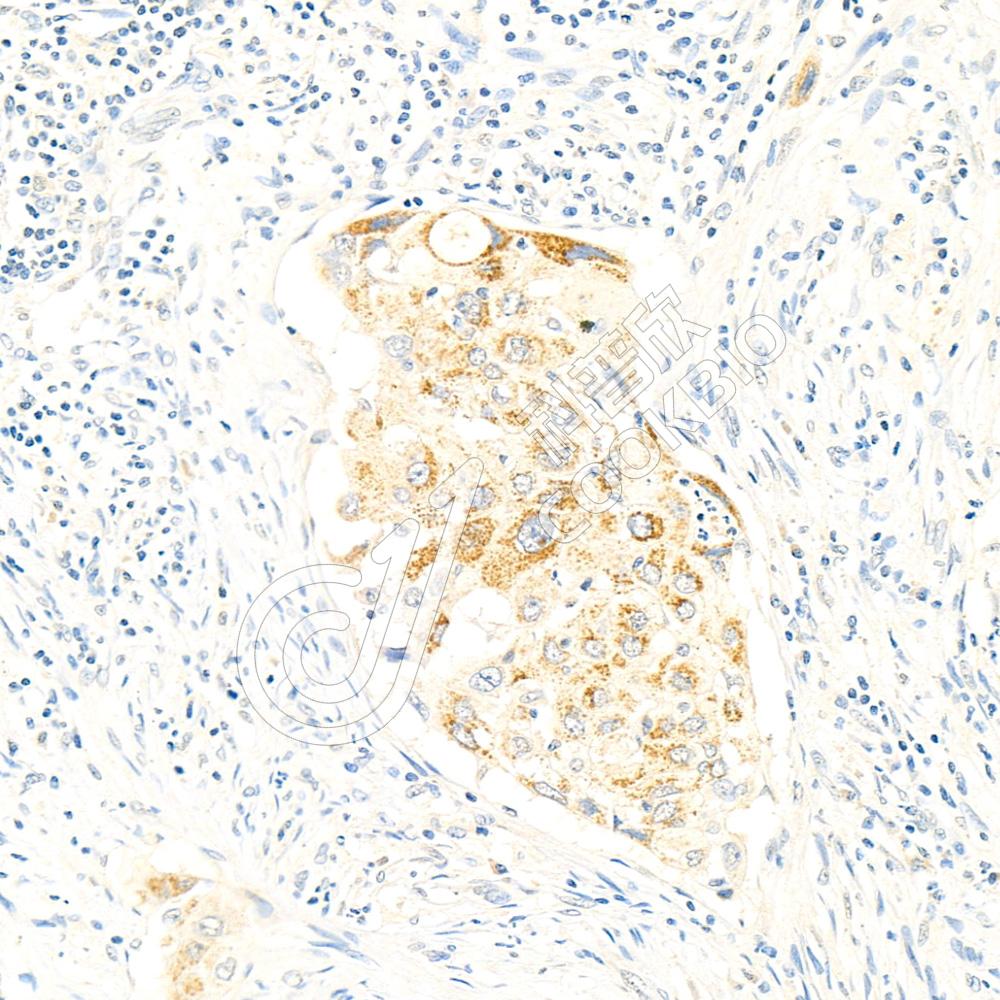

IHC检测Carbonic Anhydrase 9/CA9蛋白(货号 K1333552).

样品: 人结肠癌, 4%多聚甲醛 (货号KSG1101) 固定12-24小时.

抗原修复: 柠檬酸抗原修复液(干粉, pH 6.0) (KSG1201), 98℃, 20分钟.

—抗: 1: 1400稀释, 4℃ 孵育过夜.

二抗: S-vision免疫组化多聚二抗(山羊抗兔),即用型 (货号KB3906), 室温孵育20分钟.